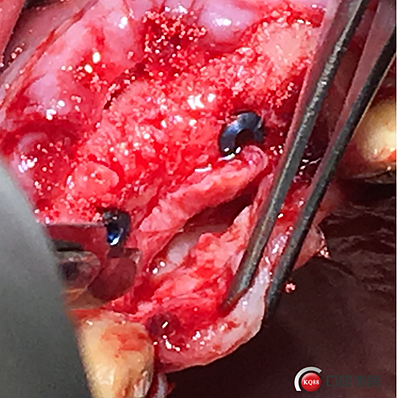

植入植體。

將骨粉塞入剝離的骨膜下間隙里既唇側(cè)倒凹處,盡量塞滿。